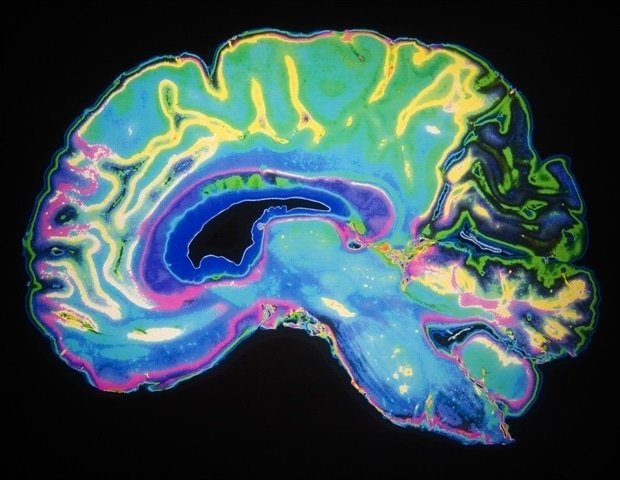

Remembering when, where, and how something happened is called episodic memory. In your brain, billions of nerve cells form a massive network, sending signals back and forth like a relay race to process information from the sensations, sounds, smells, and sights of your life.

It is already known that the hippocampus contains cells that link memory to time and space. But Verbeike and his research group had a theory that another area of the brain was also involved: the retrosplenial cortex. This region, located in the back of the cerebral cortex near the hippocampus, was previously only known as an area that links memory and place.